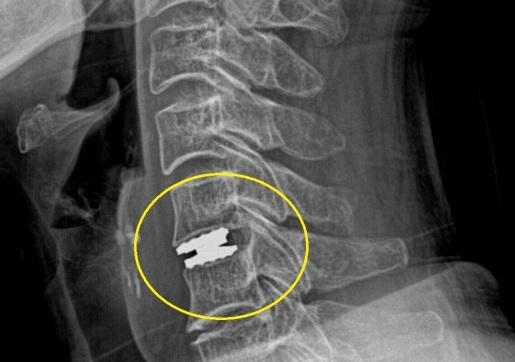

목 인공디스크 치환술 ADR(Artificial Disc Replacement) 은 손상된 디스크를 정상적인 디스크와 동일한 기능을 하게 합니다.

신경을 압박하고 있는 수핵 (디스크)를 제거하여 신경감압, 증상호전 도모 제거한 디스크 대신 인공디스크 삽입하여 탄력성 및 안정성 유지를 목적으로 합니다. 고정하는 수술이 아니므로 수술 후 관절의 기동성이 그대로 유지되어 움직임이 자유롭습니다. 목디스크 통증으로는 극심하게 아프며. 밤에 잠을 못 잘 정도로 힘듭니다. 우측 팔이 떨어져 나갈 듯한 통증, 후경부 통증. 우측 팔 통증이 심하게 나타납니다.

전신마취하에 이뤄지며 ,전방으로 접근하고 현미경하 디스크 및 신경압박 구조물 제거한 뒤 인공디스크 삽입/고정합니다. 고정하는 수술이 아니므로 수술 후 관절의 기동성이 그대로 유지되어 움직임이 자유롭습니다.